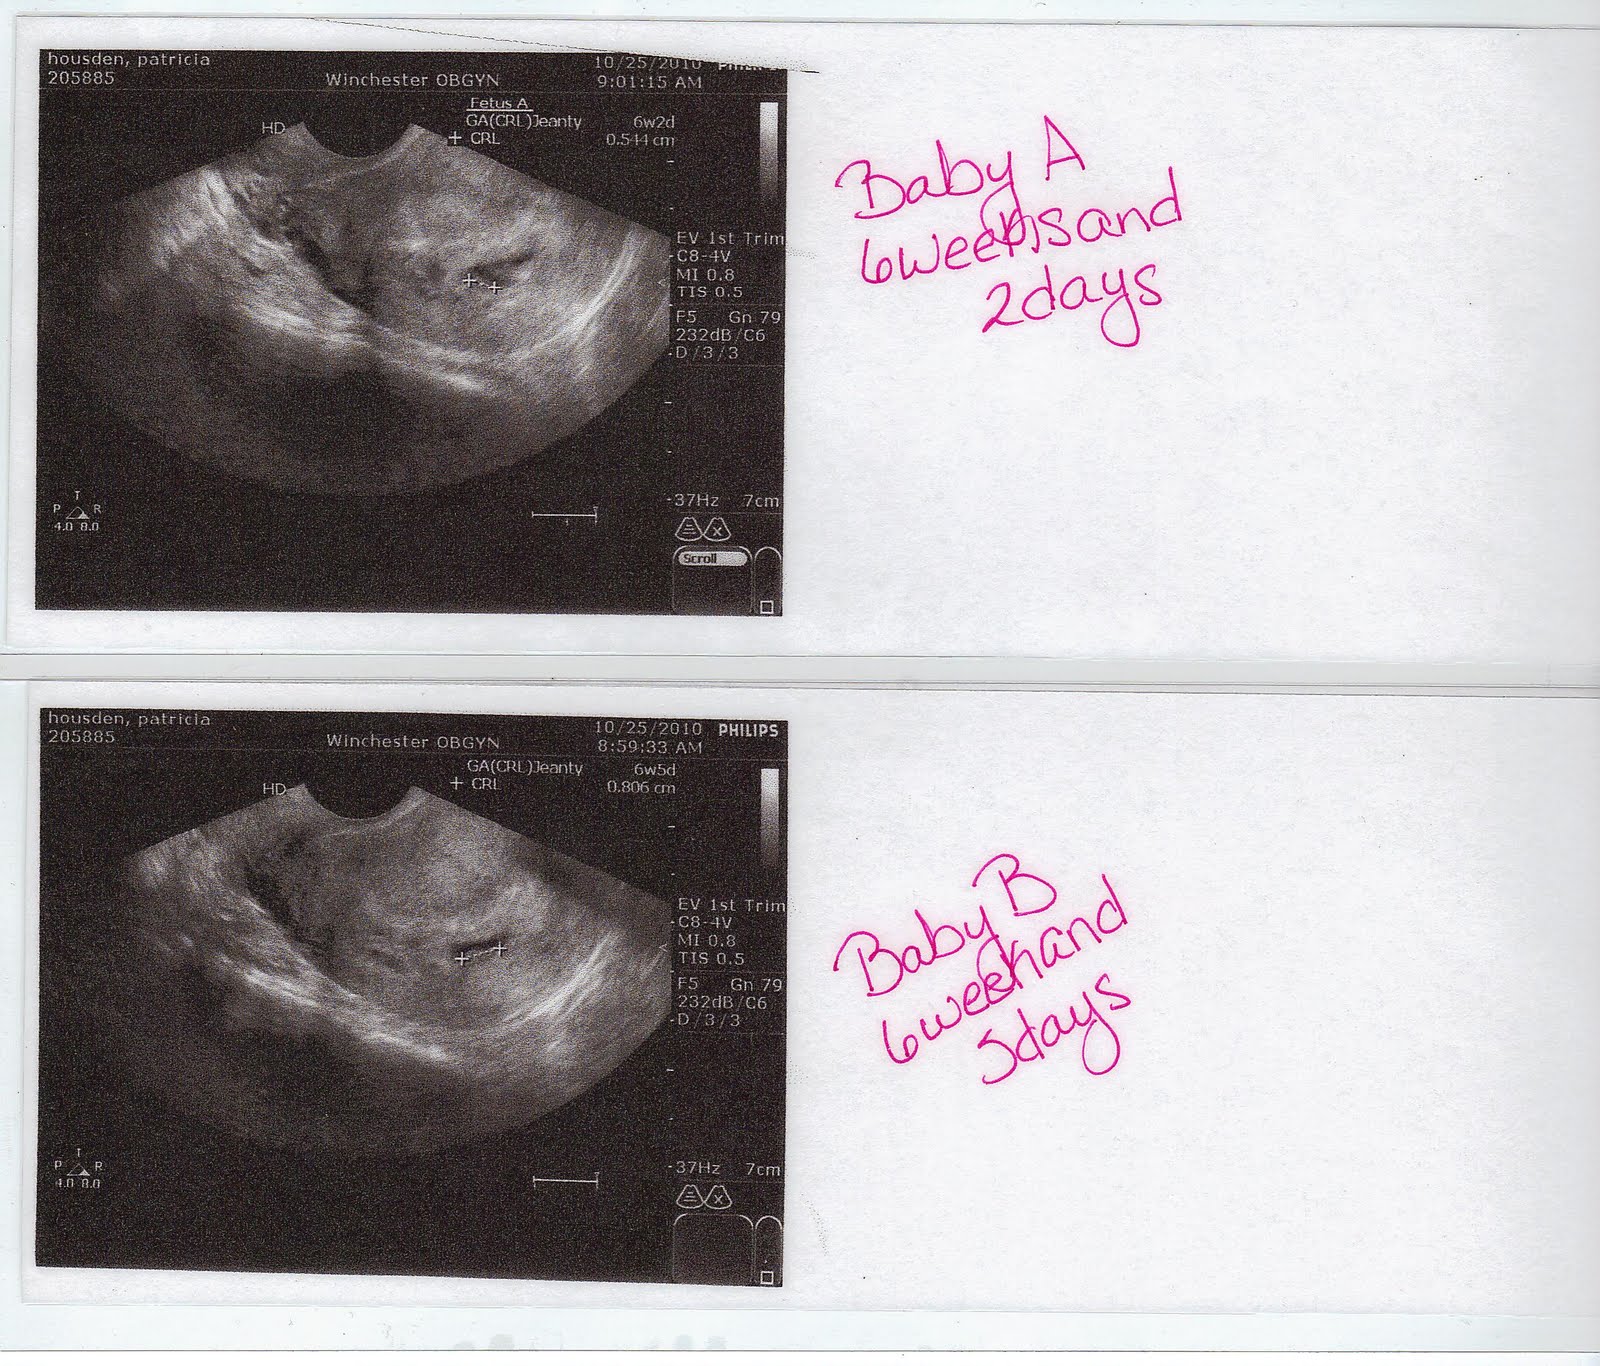

From cochranbabyaandbabyb.blogspot.com

Journey to meeting Baby A and Baby B How Do They Determine Baby A And Baby B By convention, twins are labeled as twin a or twin b at the time of birth, depending on their birth order. My babies were side by side up until about the last 3 or 4 weeks of my pregnancy. The twin assigned the title of baby a is closest to the cervix. Baby a is alway the presenting baby (the. How Do They Determine Baby A And Baby B.